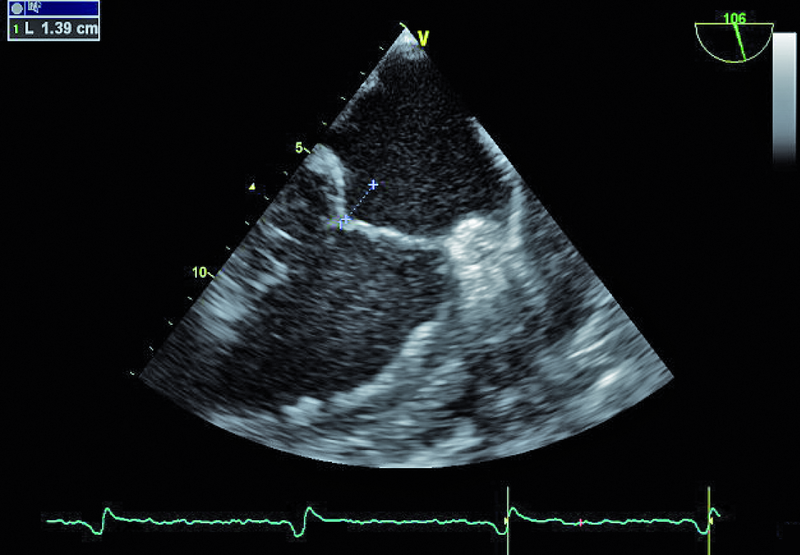

Niedomykalność zastawki mitralnej o etiologii niedokrwiennej pogarsza rokowanie u chorego z chorobą wieńcową i istotnie obniża komfort życia. Fala zwrotna w prezentowanym materiale sięga ujścia żył płucnych (ryc. 1), a ciśnienie w jamie prawej komory jest podwyższone (ryc. 2). U chorych, u których nie ma wskazań do rewaskularyzacji lub u chorych z chorobami współistniejącymi poszukuje się innych metod interwencji poza chirurgiczną naprawą. Punktem wyjścia dla rozważań o możliwości leczenia niechirurgicznego jest dokładna ocena anatomii zastawki. Wykorzystuje się dane zarówno z badania przezklatkowego, jak i przezprzełykowego, choć oczywiście optymalnym rozwiązaniem byłoby zastosowanie obrazowania trójwymiarowego. Sporo uwagi poświęca się ostatnio naprawie płatków zastawki za pomocą tzw. urządzenia mitraclip. Techniką tą można interesować się zwłaszcza w kontekście chorych bez istotnego poszerzenia pierścienia zastawki (w prezentowanym przypadku średnica pierścienia nie przekraczała 35 mm), a z dostatecznie dużą ilością tkanki tworzącej jej płatki. Założeniem techniki mitraclip, przypominającej zabieg chirurgiczny Alfieriego, jest połączenie segmentów środkowych płatka przedniego i tylnego. Skutecznie wykonany zabieg poprawia koaptację płatków i zapoczątkowuje odwrotny remodeling lewej komory, zmniejszający z kolei udział tzw. sił pociągających. Na co trzeba zwrócić uwagę, oceniając pacjenta z niedomykalnością mitralną, towarzyszącą chorobie niedokrwiennej? Niedomykalność (wg podziału Carpentiera typ 3b) powinna rzeczywiście powstawać między segmentami A2 a P2 (ryc. 3), ponieważ tylko w takim wypadku połączenie płatków i wytworzenie dwóch osobnych ujść może choremu przynieść korzyść. Ważnym elementem oceny jest uzyskanie projekcji przezżołądkowej poprzecznej. Ta projekcja bardzo dobrze ilustruje wielkość płatków i ich wzajemną relację (ryc. 4 – większy płatek tylny znajduje się bliżej głowicy). Przeciwwskazaniami do zabiegu implantacji mitraclip może być nadmierna grubość płatków, utrudniająca ich uchwycenie przez ramiona urządzenia, mniejsza niż 2 mm długość koaptacji oraz większa niż 11 mm głębokość koaptacji w stosunku do linii podstawnej pierścienia zastawki. Wymienionych cech nie potwierdzono w badaniu (ryc. 5, 6) i zakwalifikowano chorego do zabiegu w trybie planowym. Warto pamiętać, że echokardiografia służy nie tylko ocenie wskazań do zabiegu, ale stanowi także podstawę jego monitorowania.